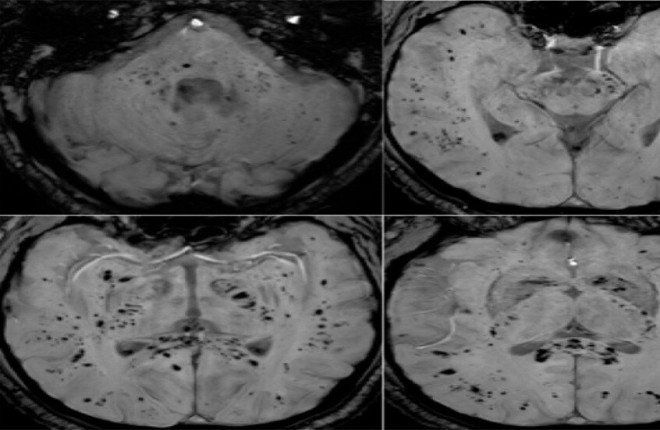

كشفت دراسة علمية حديثة، استندت إلى تحليل صور بالرنين المغناطيسي، أن فيروس كوفيد-19 قد يترك آثارًا مستمرة على الدماغ، تمتد حتى بعد التعافي التام من الإصابة، بما في ذلك الحالات التي لم تُسجَّل لديها أعراض واضحة.

وأظهرت الدراسة، التي أجراها باحثون من جامعة غريفيث الأسترالية ونُشرت في مجلة Brain، Behavior، & Immunity Health، أن تأثير كوفيد-19 لا يقتصر على الجهاز التنفسي فقط، بل يشمل تغيّرات ملموسة في أنسجة الدماغ، حتى لدى الأشخاص الذين يعتبرون أنفسهم متعافين تمامًا.

وأوضح الباحث الرئيسي، الدكتور كيران تاباليا، أن فريق الدراسة استخدم تقنيات متقدمة للتصوير بالرنين المغناطيسي متعددة الوسائط، بهدف تحليل المادة الرمادية والبيضاء في الدماغ، وهما عنصران أساسيان للذاكرة والوظائف الإدراكية والصحة العامة للجهاز العصبي.

وبيّنت النتائج وجود اختلافات واضحة في أنسجة الدماغ، والمواد الكيميائية العصبية، وشدة الإشارات العصبية، إضافة إلى بنية الأنسجة، لدى المتعافين من كوفيد-19، حتى في حالات الإصابة الخفيفة. وأشار تاباليا إلى أن هذه التغيرات ترتبط بدرجة شدة الأعراض التي عانى منها المصابون، ما قد يفسر استمرار مشكلات إدراكية طويلة الأمد، مثل ضعف الذاكرة وصعوبة التركيز.

وأضاف الباحث أن هذه التأثيرات قد تستمر لأشهر، وربما لسنوات بعد الإصابة، ما يسلّط الضوء على الأبعاد العصبية بعيدة المدى للفيروس.